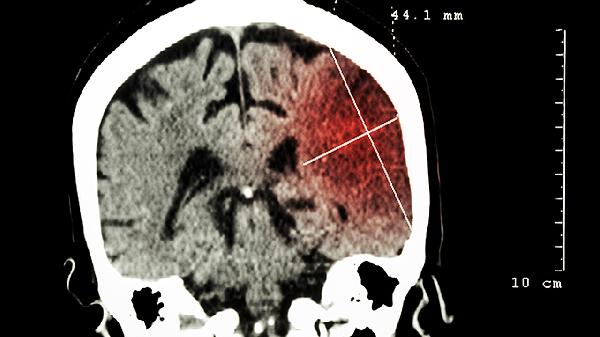

腦瘤早期癥狀主要有頭痛、惡心嘔吐、視力障礙、癲癇發(fā)作和肢體無力等。腦瘤是指顱內(nèi)異常生長的腫瘤,可能壓迫腦組織或神經(jīng),引發(fā)一系列癥狀。

腫瘤壓迫視神經(jīng)或視交叉可能導致視力下降、視野缺損或視物模糊。部分患者會感覺眼前有閃光或黑影,這種視覺異常通常呈進行性加重。定期眼科檢查和頭顱影像學篩查有助于早期發(fā)現(xiàn)病變。